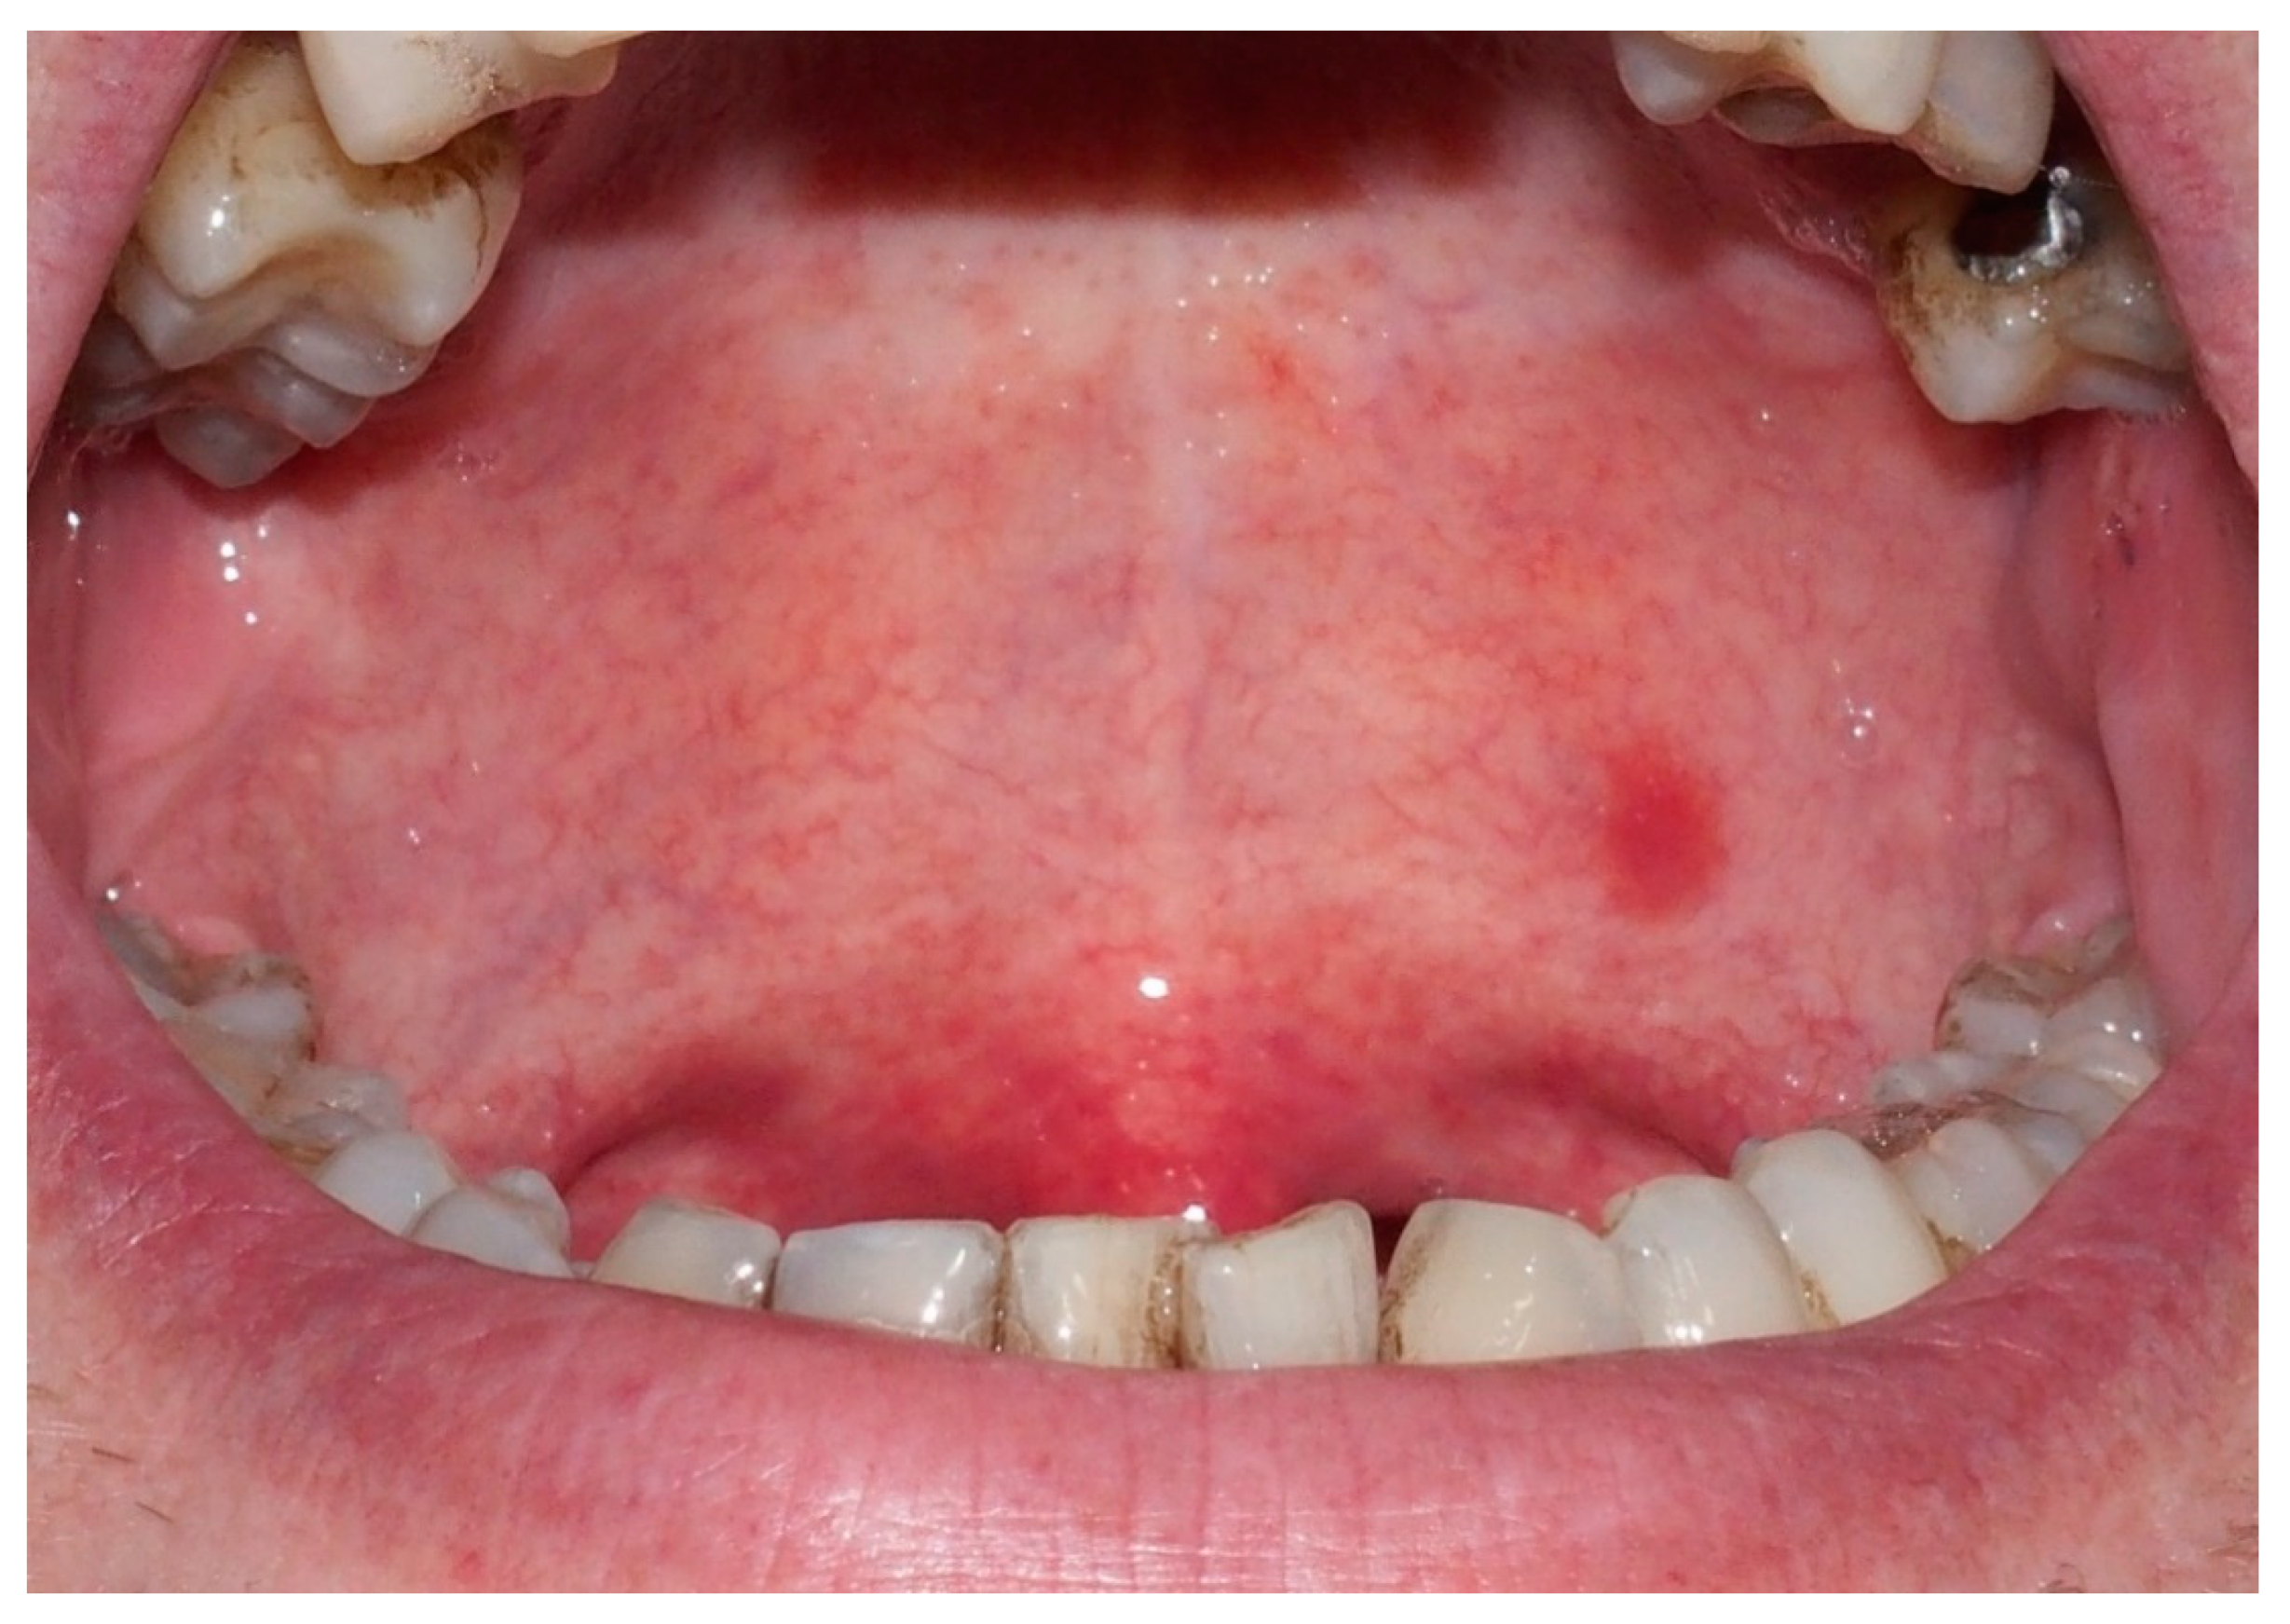

Solitary Extramedullary Plasmacytoma Presenting as Asymptomatic Palatal Erythroplakia: Report of a Case

2. Case Report